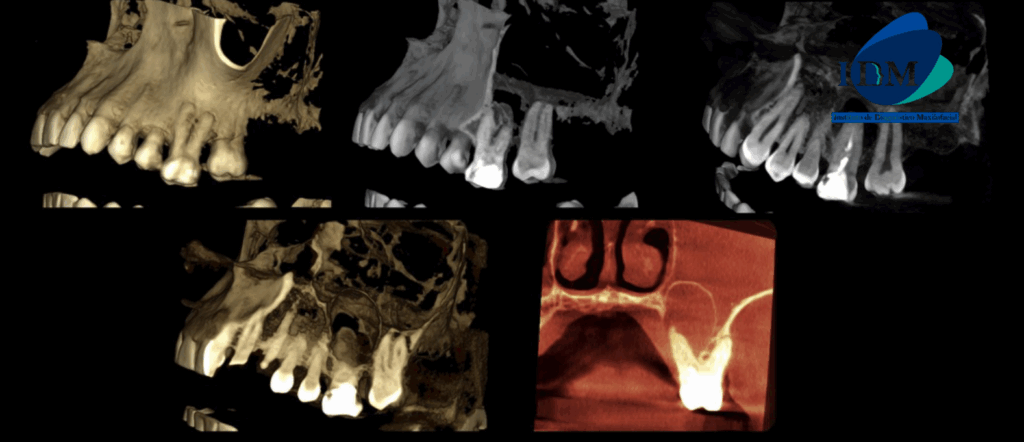

A la evaluación de la tomografía computarizada en cortes axiales, transaxiales y tangenciales se observa la pieza 16 con la raíz mesiovestibular con una obturación parcial y sobre extendida del conducto, asimismo presenta un conducto colateral obliterado y un proceso osteolítico periapical y reabsorción radicular externa del tercio apical; la raíz distovestibular presenta también una obturación parcial de conducto y la raíz palatina presenta un espigo intrarradicular, obturación parcial y subextendida del conducto y una imagen hipodensa corticalizada que desplaza hacia cefálico el piso de seno maxilar y compromete la tabla ósea palatina compatible con quiste radicular, asimismo ocasiona un engrosamiento de la mucosa antral ipsilateral compatible con sinusitis de origen odontogénico.

RECONSTRUCCIÓN 3D